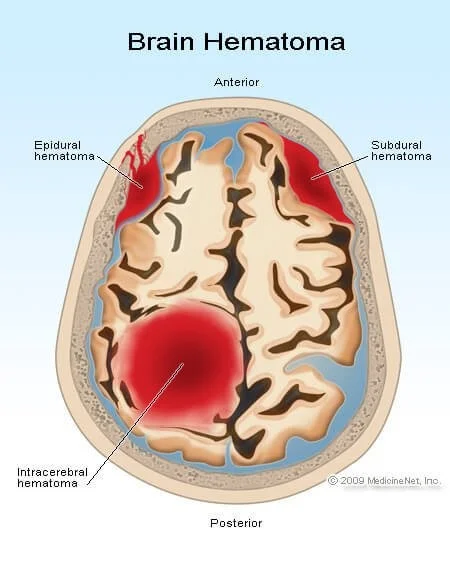

Intracranial hematoma:

Is a collection of blood within the skull, most commonly caused by rupture of a blood vessel within the brain or from trauma. There are four types:

- Epidural hematoma.

- Subdural hematoma.

- Subarachnoid hemorrhage.

- Intracerebral hemorrhage.

Epidural hematoma

Is a traumatic accumulation of blood between the inner table of the skull and the outer covering of the brain called (dura).

Subdural Hematoma

Is a collection of blood below the inner layer of the dura but external to the brain and arachnoid membrane.

Intracerebral Hemorrhage

Is when blood suddenly bursts into brain tissue, causing damage to the brain.